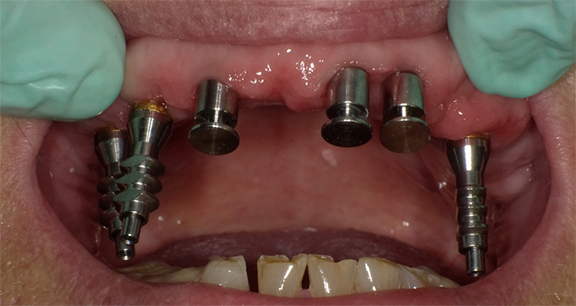

Four months later, overdenture attachments that permitted angle correction up to 60 degrees were attached to the implants by using a hex driver and were torqued per the manufacturer's recommendation (Figure 11).41 The attachments had a small screw-access hole that prevented food entrapment. Attachments are available in various heights.41 The height of each attachment should be predetermined by measuring the distance between the platform of the implant and the crest of the peri-implant tissue (Figure 12).47

An implant-retained and implant-supported removable prosthesis may be fabricated by using a bar or a conical, titanium abutment with a 5-degree taper (Figure 18).49 In the next case, a fixture-level impression was made and records were registered and sent to the laboratory with the abutments (preselected based on the height of the mucosal cuff) for framework and prosthesis fabrication.49 The prosthesis had recesses on its intaglio surface to permit pickup of the abutment caps (Figure 19).49 The abutments were attached to the implants in the mouth (Figure 20). A jig/index provided by the laboratory (Figure 21) was used to seat the abutments intraorally so that they were positioned exactly as they were on the master cast. Gold caps were placed over the abutments and were picked up in the prosthesis intraorally (Figure 22).49 (Gold caps that fit over the abutments provide excellent retention, which improves over time.)50 The prosthesis was adjusted, finished, polished, and placed in the mouth (Figure 23). The prosthesis was entirely supported by the implant abutments.49 It had excellent retention and stability (almost like a fixed restoration) because it was entirely implant-supported; yet, it was removable.49